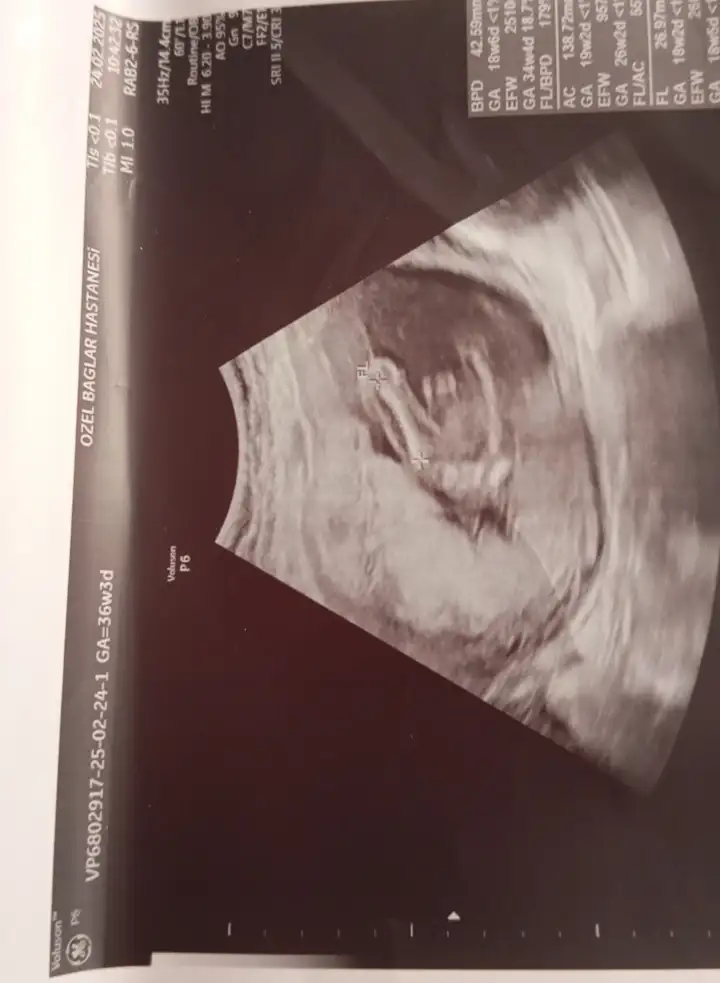

Arkadaşlar lütfen benimkisinde bakarmısınız 12. Haftada erkeğe benziyor dendi bu 12. Haftalık ultrason 16 haftada kız dendi sizce nedir

Eklentiler

• CAP_6B9B2076-EB37-4588-9FE9-C2183774154C.webp

16,8 KB · Görüntüleme: 848